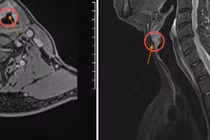

Cha chị Lan, ông Khâu, 70 tuổi, khàn tiếng kéo dài, uống thuốc không khỏi nên đến khám tại Bệnh viện Đa khoa Tâm Anh TP HCM. TTND.GS.TS.BS Trần Phan Chung Thủy, Giám đốc Trung tâm Tai Mũi Họng, nội soi hoạt nghiệm thanh quản ống mềm thấy tổn thương dạng u sùi mép trước dây thanh, chỉ định lấy mẫu sinh thiết.

Kết quả, ông Khâu bị ung thư dây thanh trái, dạng biểu mô tế bào vảy, giai đoạn T2.

Kỹ thuật ít xâm lấn bảo tồn chức năng dây thanh

GS.TS Chung Thủy chỉ định phẫu thuật laser CO2 cho người bệnh. Đây là kỹ thuật vi phẫu xâm lấn tối thiểu, áp dụng cho ung thư ở giai đoạn sớm, tỷ lệ tái phát thấp, không cần xạ trị sau mổ. Phương pháp thực hiện qua đường miệng giúp cắt bỏ triệt để khối u ung thư, không cần mổ mở, bảo tồn được chức năng thanh quản, giúp người bệnh hồi phục tốt hơn.